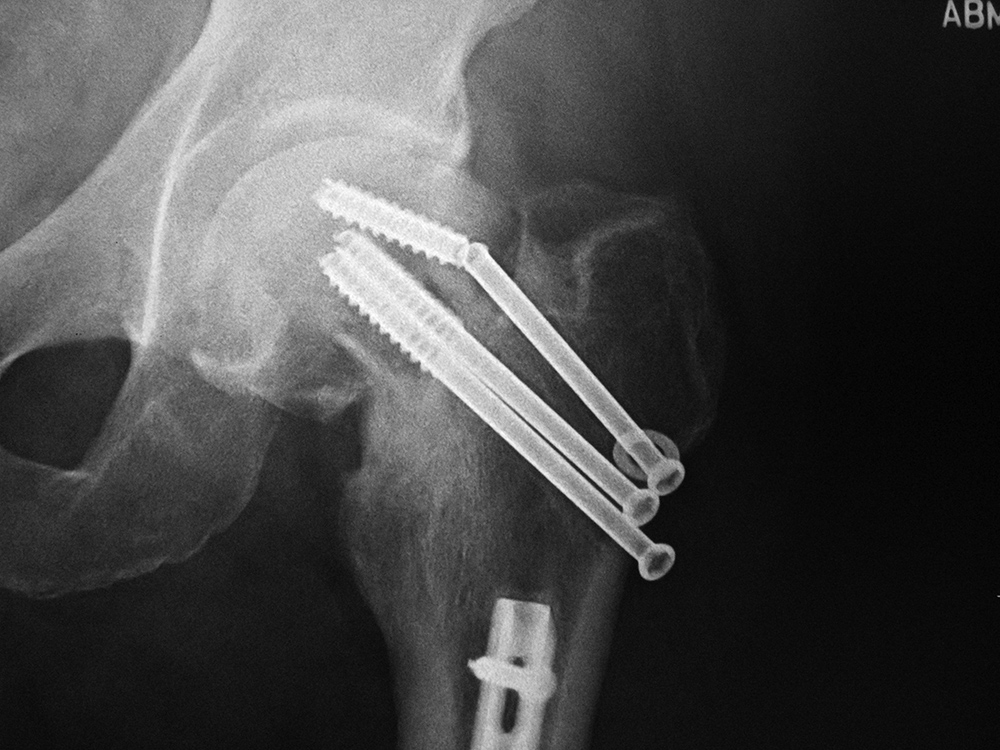

| Left hip cannulated screw fracture |

| 41 year-old man with chronic left femoral neck fracture and fracture of superior cannulated fixation screw. The partially visualized intramedullary nail is for an old femoral shaft fracture. |